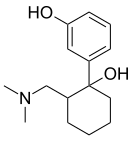

The pharmacodynamic response to an opioid depends upon the receptor to which it binds, its affinity for that receptor, and whether the opioid is an agonist or an antagonist. For example, the supraspinal analgesic properties of the opioid agonist morphine are mediated by activation of the μ1 receptor; respiratory depression and physical dependence by the μ2 receptor; and sedation and spinal analgesia by the κ receptor. Each group of opioid receptors elicits a distinct set of neurological responses, with the receptor subtypes (such as μ1 and μ2 for example) providing even more [measurably] specific responses. Unique to each opioid is its distinct binding affinity to the various classes of opioid receptors (e.g. the μ, κ, and δ opioid receptors are activated at different magnitudes according to the specific receptor binding affinities of the opioid). For example, the opiate alkaloid morphine exhibits high-affinity binding to the μ-opioid receptor, while ketazocine exhibits high affinity to ĸ receptors. It is this combinatorial mechanism that allows for such a wide class of opioids and molecular designs to exist, each with its own unique effect profile. Their individual molecular structure is also responsible for their different duration of action, whereby metabolic breakdown (such as N-dealkylation) is responsible for opioid metabolism.

Several semi-synthetic opioids were developed in Germany in the 1910s. The first, oxymorphone, was synthesized from thebaine, an opioid alkaloid in opium poppies, in 1914.[228] Next, Martin Freund and Edmund Speyer developed oxycodone, also from thebaine, at the University of Frankfurt in 1916.[229] In 1920, hydrocodone was prepared by Carl Mannich and Helene Löwenheim, deriving it from codeine. In 1924, hydromorphone was synthesized by adding hydrogen to morphine. Etorphine was synthesized in 1960, from the oripavine in opium poppy straw. Buprenorphine was discovered in 1972.[228]

The first fully synthetic opioid was meperidine (later demerol), found serendipitously by German chemist Otto Eisleb (or Eislib) at IG Farben in 1932.[228] Meperidine was the first opiate to have a structure unrelated to morphine, but with opiate-like properties.[199] Its analgesic effects were discovered by Otto Schaumann in 1939.[228] Gustav Ehrhart and Max Bockmühl, also at IG Farben, built on the work of Eisleb and Schaumann. They developed "Hoechst 10820" (later methadone) around 1937.[230] In 1959 the Belgian physician Paul Janssen developed fentanyl, a synthetic drug with 30 to 50 times the potency of heroin.[211][231] Nearly 150 synthetic opioids are now known.[228]